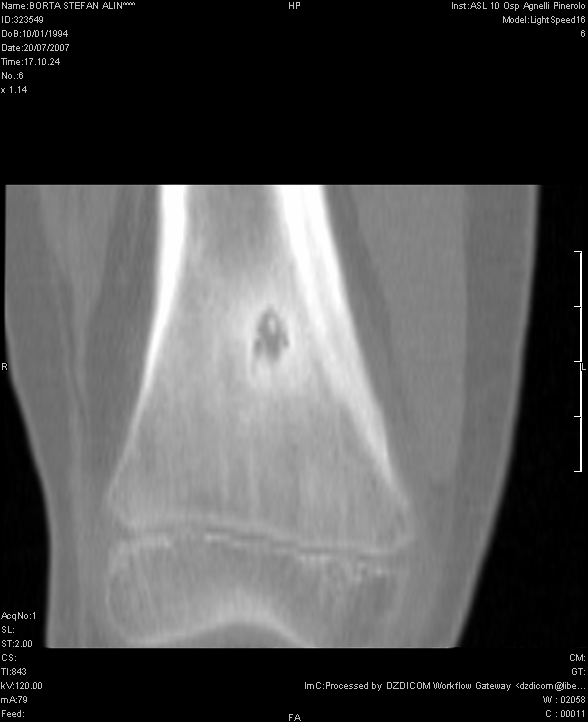

S. veniva

dunque ricoverato presso il nostro Reparto di Pediatria. Gli esami di

laboratorio inizialmente eseguiti erano normali e la radiografia del

ginocchio non evidenziava anomalie. Veniva eseguita una TAC dell'arto

inferiore dx che evidenziava una lesione di circa 5 mm di diametro a

livello della corticale del femore distale, compatibile con OO

(Figura 1). In seguito la scintigrafia

Figura

1. La TC del femore dx dimostra la presenza in sede

iuxtametafisaria di addensamento della trabecolatura ossea che

circoscrive un'area di maggior radiotrasparenza.